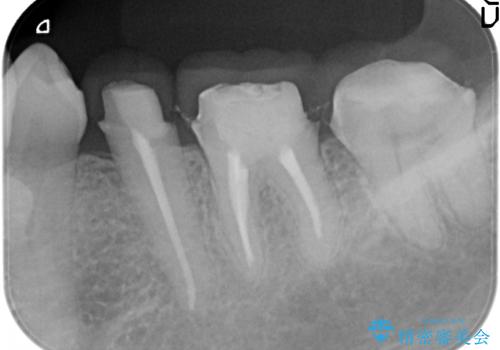

- 違和感や疼きのある左側小臼歯に加え全体的にクラウンや詰め物のやりかえを希望され来院されました。

治療後に再発した虫歯や根管再治療に加え、穴の空き症状のある上顎左側小臼歯は抜去を行いインプラントによる機能回復治療を計画します。

X線写真検査ではわからない虫歯も外してみると再発していることがあります。虫歯を丁寧に取り除き、再発を防ぐべく精密なクラウンの作製を行うことが長期的な予後につながります。